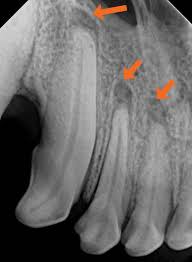

infrabony pockets

occurs when vertical bone loss is present

classified into infra-bony defects or osseous defects

JE is located apical to the crest of the alveolar bone

suprabony pockets

occurs when horizontal bone loss is present

base of the periodontal pocket is coronal to the alveolar crest

JE is located coronal to the crest of the alveolar bone